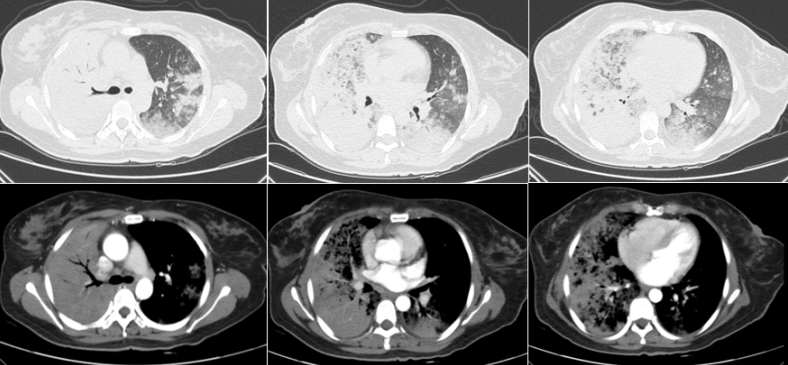

59岁男性患者,咳嗽、胸闷2年余。诊断肺结核3年,规律抗结核治疗1年。有大理石切割职业史5年,脱离该职业10余年。入院氧合指数为200~300 mmHg,多项肿瘤指标升高,自身抗体阴性。胸部CT示双肺弥漫性磨玻璃影,索条影,小叶间隔增厚图5

图片

图5  患者胸部CT

初步诊断:急性间质性肺炎?肺结核复发?肿瘤肺转移?矽肺?